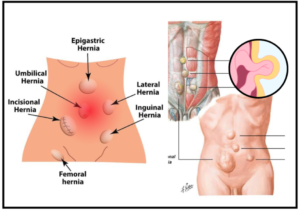

Read MoreHernia Surgery

What is Hernia? The bulging of an internal organ or...